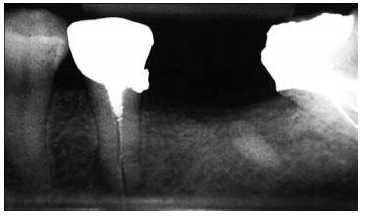

圖3:上頜第二前磨牙,牙根里非常短的樁

盡管短樁從未被提倡使用,但是研究發(fā)現(xiàn)經(jīng)常能在根尖片上觀(guān)察到短樁的存在(圖 3)。臨床上發(fā)現(xiàn)在327例樁修復(fù)當(dāng)中,僅僅有34%的樁長(zhǎng)度與冠上切-頸長(zhǎng)度相當(dāng),即冠與樁長(zhǎng)度的比例為1:1。一項(xiàng)研究曾對(duì)200例牙髓治療后的牙齒進(jìn)行評(píng)估,結(jié)果顯示僅僅14%的樁長(zhǎng)度為牙根長(zhǎng)度的2/3或者長(zhǎng)于牙根長(zhǎng)度的2/3。另外一項(xiàng)根尖片研究結(jié)果表明樁修復(fù)中,樁長(zhǎng)度為牙根長(zhǎng)度的2/3或者3/4的比例僅占5%。當(dāng)臨床上應(yīng)用短樁修復(fù)時(shí),由于高應(yīng)力的原因,牙根常常會(huì)發(fā)生折斷,反之,增加樁的長(zhǎng)度能夠提高牙根的抗折能力。